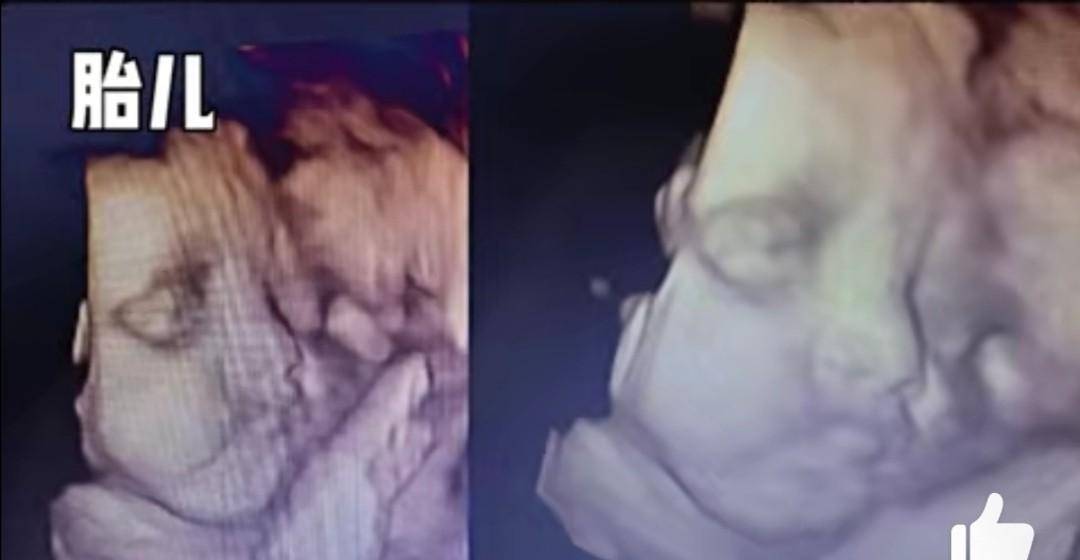

男宝16周b超图,男宝女宝b超图区别图

张兆艺还晒出了宝宝的b超照片,宝宝的五官清晰地呈现在屏幕上,可以